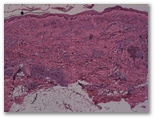

R3-1514-Mujer de 35 años, sin antecedentes patologicos relevantes que consulta por adenopatías hiliares y las lesiones cutáneas que observas en la imagen y en la biopsia.

a)descripción, dx, formas clínico-patologicas

Diagnostico